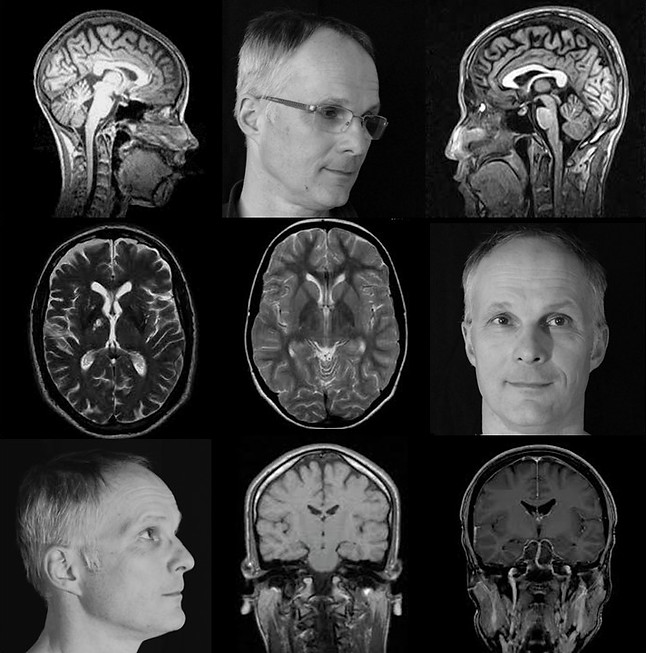

I am a strange loop

g1a.jpg

g1b.jpg